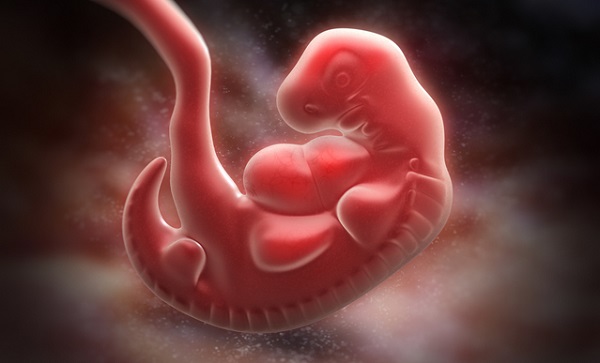

妊娠4~16週は、大切な器官や組織がハイペースで形成されるため、「器官形成期」とも呼ばれます。

妊娠5週目から9週にかけて、顔のパーツが形成され始めます。頭の部分には、耳ができる場所にくぼみが現れ、目となる組織ができます。胃や腸、膵臓、肺の形成もスタートします。

また、心臓につながる大動脈の形成が始まり、すべての器官に心臓から血液を運べるようになります。

胎芽の大きさと形

胎芽の頭骨の頂点からお尻までの長さを「頭臀長(とうでんちょう)」と言いますが、この頃の頭臀長はわずか3~5mm程度です。

5週目の終わり頃には、赤ちゃんは「く」の字のような体勢で、腕となる部分が盛り上がってきます。また体の成長が脊髄の成長に追いつくに従い、お尻のしっぽのような部分が目立たなくなってきます。